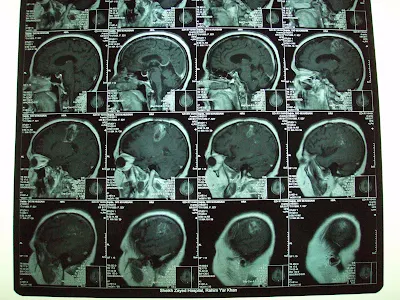

| Oligodendroglioma, Grade III (Recurrent)Before Gamma Knife |

This 45 years old Lady had undergone left frontal Craniotomy in November 2009 on diagnosis of left frontoparietal tumor,. On histopathology it was Anaplastic Oligodendroglioma, WHO grade III. She had tonic clonic fits and right hemiparesis. she had received Radiotherapy to left hemisphere using left lateral and posterior fields on 6Mv X-ray beam. Total dose of 60 Gy in Multiple fractions of 200 cGy had received until March 1, 2010. Temozolamide as conjoined chemotherapy used for 6 weeks during radiotherapy and 3 cycles after one month of radiotherapy.

On referral, for She had presented progressive recurrence of right hemiparesis and fits since first week of April 2010. On Clinical examination, she had House Brackmann right facial palsy grade I-II and right hemiplegia. MRI brain with contrast had revealed multiple heterogeneous rim enhancing mass in the left parietal region with significant perilesional edema. Patient referred us for management with GKSRS. Risk of GKSRS explained. These agreed upon wished to proceed. She had treatment with following prescription.